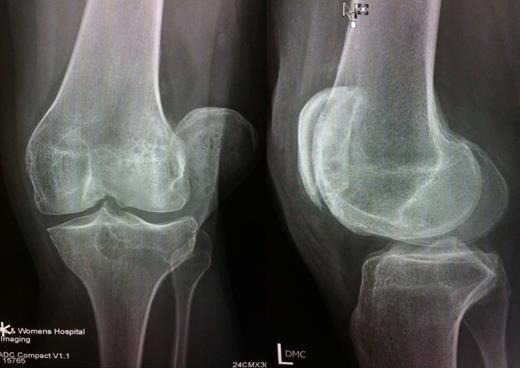

His knee was locked in full extension (unlike some flexion associated with lateral patellar dislocation) (6,8). The patella was rotated about the long axis with the smooth articular surface facing posterolaterally. It was locked under the outer edge of the lateral femoral condyle. Imaging studies confirmed the clinical findings and also revealed a minor impaction fracture of lateral femoral condyle with arthritic changes in the knee joint (Figure 2).

Imaging studies showing lateral dislocation of patella with rotation about long axis, patella locked onto lateral femoral condyle; and insignificant impaction fracture of lateral femoral condyle